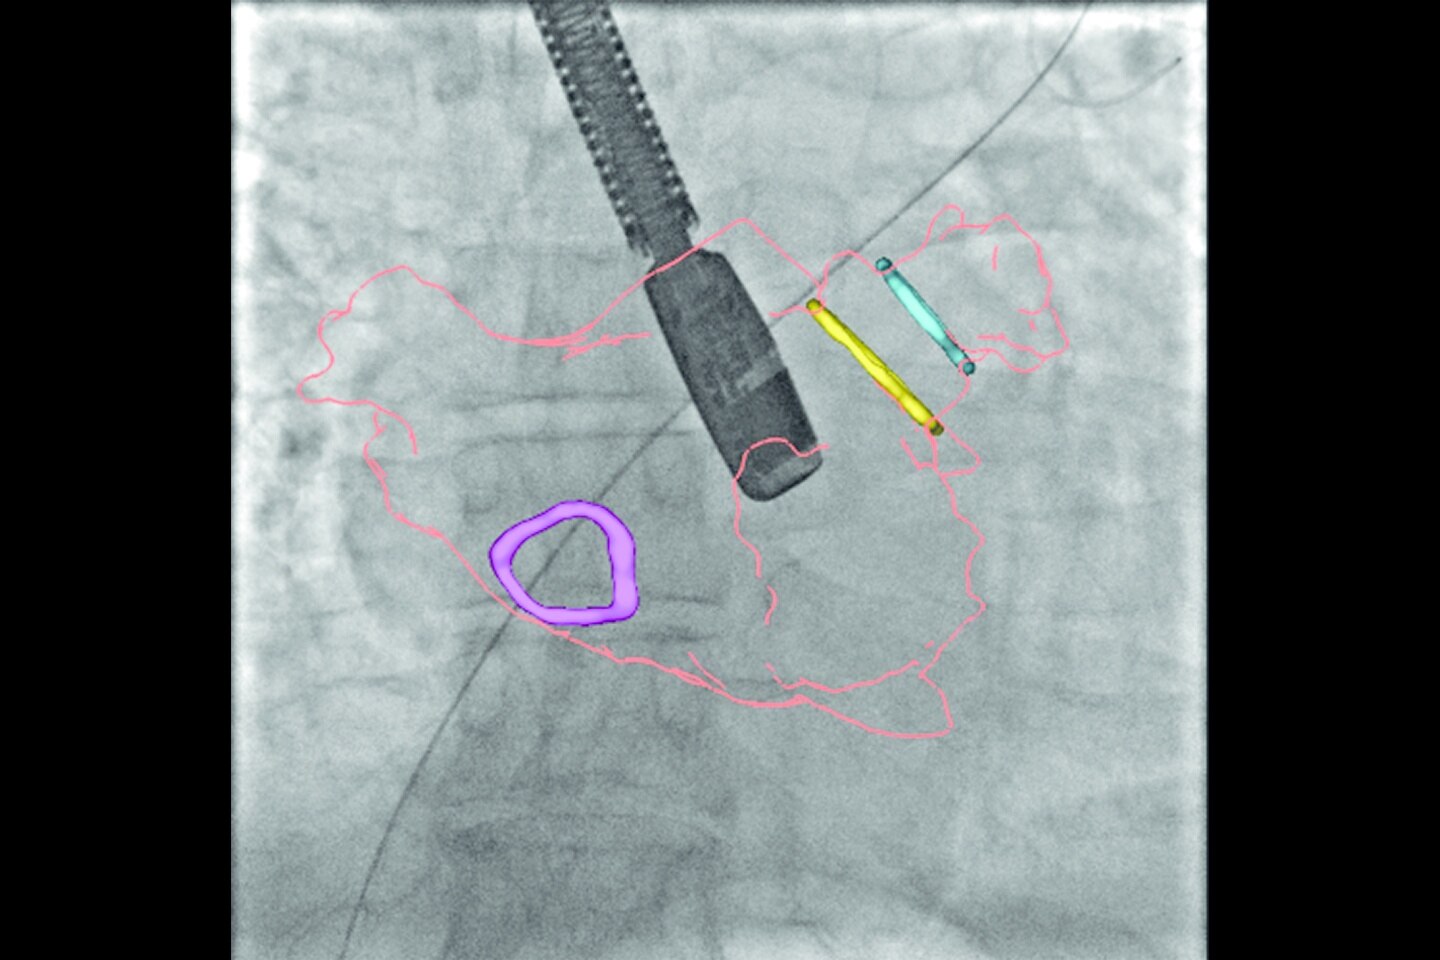

Функция автоматического позиционирования* на основе интеллектуальных алгоритмов позволяет оптимизировать рабочий процесс, сводя к минимуму необходимые действия: вам остается только нажать кнопку. После определения ключевых точек на планшете Xtream отображается диапазон предварительного сканирования, затем приводятся в движение дека и стол до тех пор, пока центр диапазона сканирования не совпадет с изоцентром КТ-системы.

Автоматическая оценка ориентиров* и отображение области предварительного сканирования

Определяет местоположение ориентиров с помощью алгоритма глубокого обучения и отображает диапазон предварительного сканирования на планшете Xtream

Автоматическое центрирование*

Определяет центр диапазона предварительного сканирования и выравнивает его с изоцентром КТ-системы. Уменьшает необходимость в повторном позиционировании пациента и проведении повторного предварительного сканирования благодаря высокой точности

Автоматическое позиционирование пациента*

Интеллектуальные алгоритмы позволяют автоматически переместить пациента в нужное положение перед началом сканирования. Оптимизирует рабочий процесс, сводя позиционирование пациента к одному клику